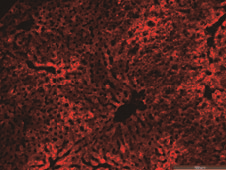

肝脏

心脏

肺部